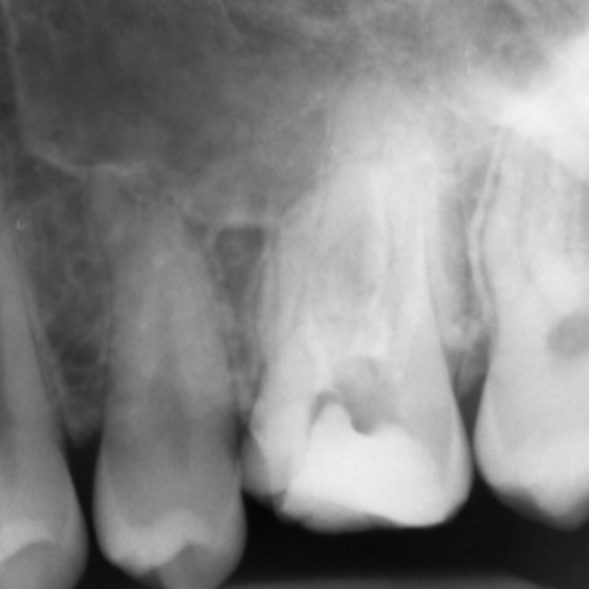

Figure 4: Patient was referred for the root canal retreatment of UR6. The tooth had been treated privately with her general dentist three years ago; the root canal treatment had been carried out to a good standard (under rubber dam isolation, three canals cleaned, shaped, disinfected using sodium hypochlorite and obturated to length). The patient did not have significant pain but the tooth did not ‘feel right’ and was affecting her function. Root canal retreatment was carried out and an additional MB2 canal was located. The patient’s symptoms settled immediately following treatment and she was advised to proceed with a cuspal coverage restoration.

A missed MB2 canal is one of the main causes of endodontic failure in maxillary molars. In cases of irreversible pulpitis, it is responsible for ongoing temperature sensitivity. In necrotic cases, residual bacteria will increase the risk of infection (Figure 4).